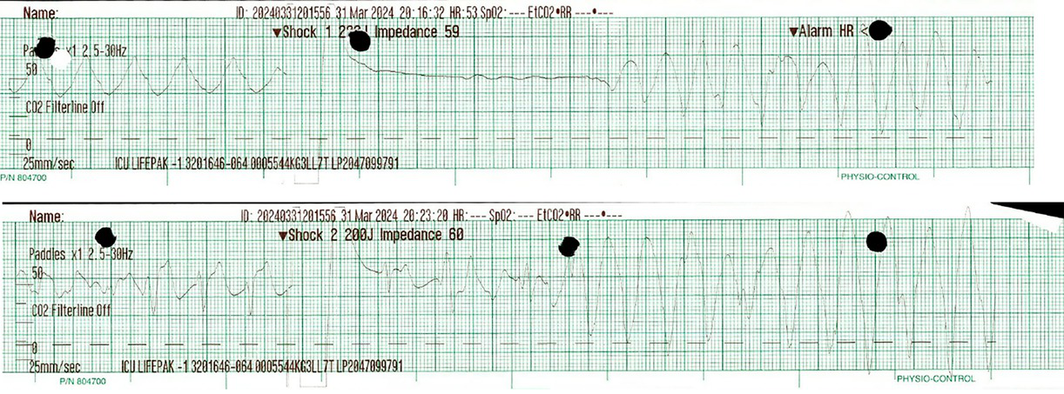

Two hours later and on arrival to the intensive care unit, a second cardiac arrest occurred due to recurrence of hyperkalaemia (potassium concentration of 7.2 mmol/L). CPR was performed for 11 minutes, including two defibrillator shocks of 200 J, resulting in RoSC (Box 3). Further treatment was given: